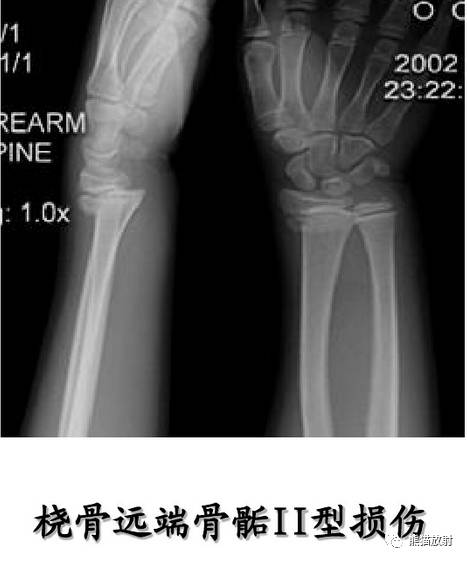

II型:骨骺分离伴干骺端骨折(最多见)

Salter-Harris II型:骨折累及骺板及干骺端,骨骺骨折中最多见(75%),预后较差。

第二型(Ⅱ型) 骨骺分离伴干骺端骨折。该型损伤最多见,占骨骺损伤的48.2%,好发部位在桡骨远端、肱骨近端及胫骨远端。多发生在10一16岁的儿童,骨折线通过肥大并累及干骺端的一部分,骨折片呈三角形,在骨折端成角之凸侧有骨膜撕裂,而凹侧骨膜完整、复位容易,预后良好。